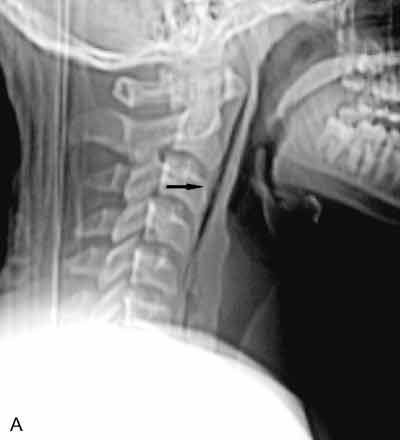

2. Throat pain in a catcher hit with a bat: The lateralradiograph reveals a large, linear collection of gas within theretropharyngeal soft tissues (A, arrow). There are 4 possibleexplanations for gas in a location in which it does notnormally occur:

In this patient, a laryngeal injury is suspected.You order a CT scan of the neck to further investigatethis possibility. An axial image filmed in bone windowsat the level of the thyroid (B) and an axial image filmedin soft tissue windows at the level of the mandible (C)confirm the finding of retropharyngeal gas (arrows).However, no clearly defined track of gas extends fromthe esophagus or trachea. There is also no clear evidenceof hematoma.

You order a Gastrografin swallow. This anteroposteriorprojection of an esophagram at the level of the softtissues of the neck reveals a clear leakage of contrastmaterial from the cervical esophagus at approximatelythe level of the C6 vertebral body (D, arrow).